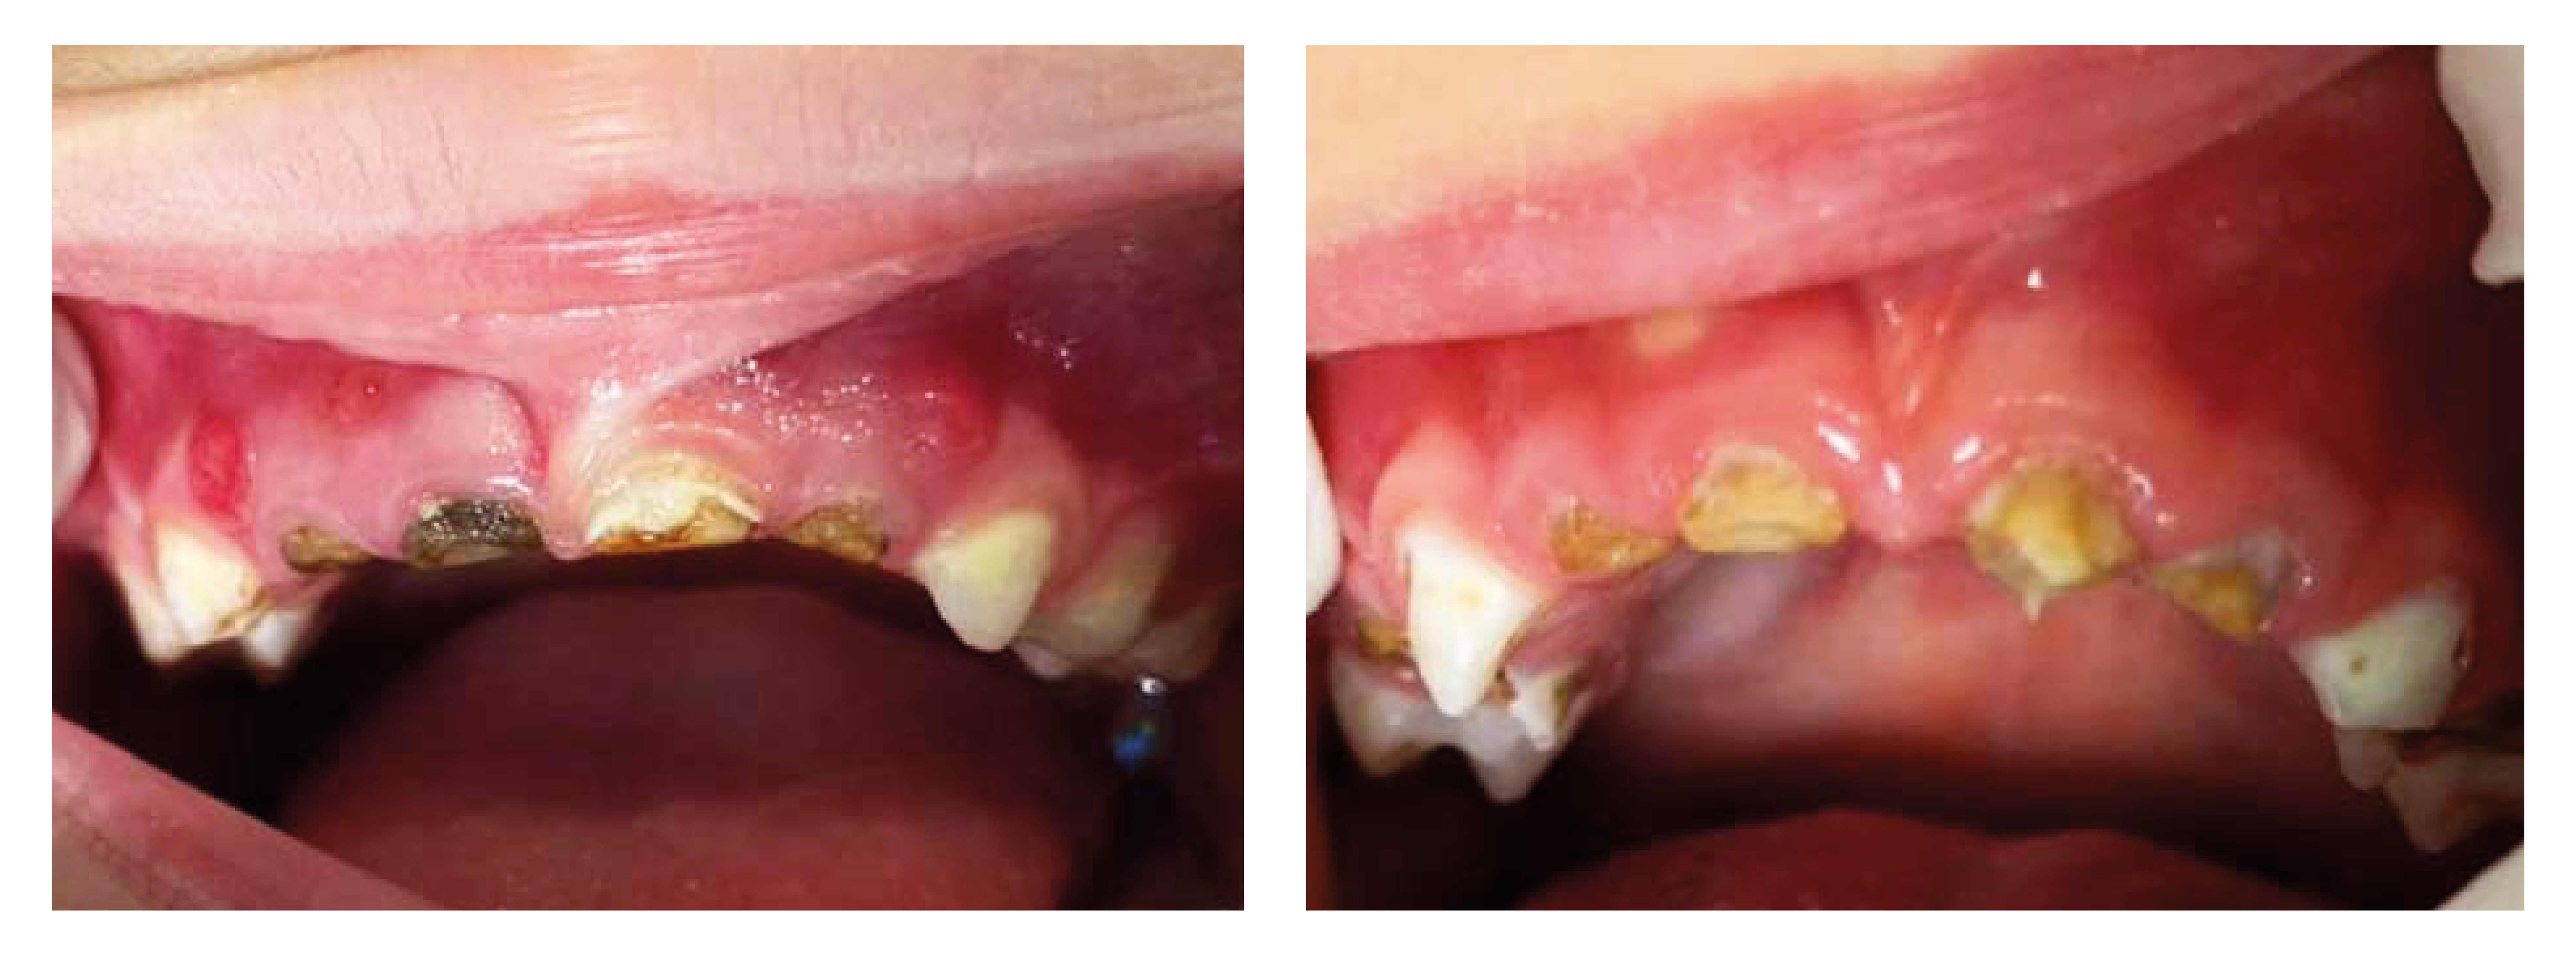

La primera manifestación de la caries de infancia temprana es una mancha blanca en forma de media luna o semicírculo en la parte superior del diente cerca a la encía, pronto la mancha cambiará a un color amarillo claro o negro y comenzará a extenderse hacia los lados y hacia abajo como se muestra a continuación:

*Caries de infancia temprana en su etapa inicial, intermedia y en estado avanzado

Esta se caracteriza por provocar un proceso destructivo rápido de los dientes (incisivos superiores inicialmente), pues la capa de esmalte dental de los dientes de leche es mucho más delgada y débil que la de los dientes permanentes, además anatómicamente son mucho más pequeños por lo que la caries llega con mayor rapidez al nervio, aumentando así las posibilidades de formar un absceso dental.